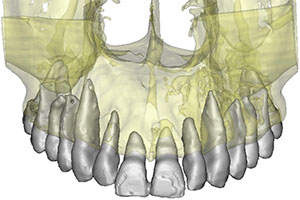

Se realiza tomografía e imagen tridimensional 3D, observamos además de la lesión traumática, que la paciente tiene raíces enanas.